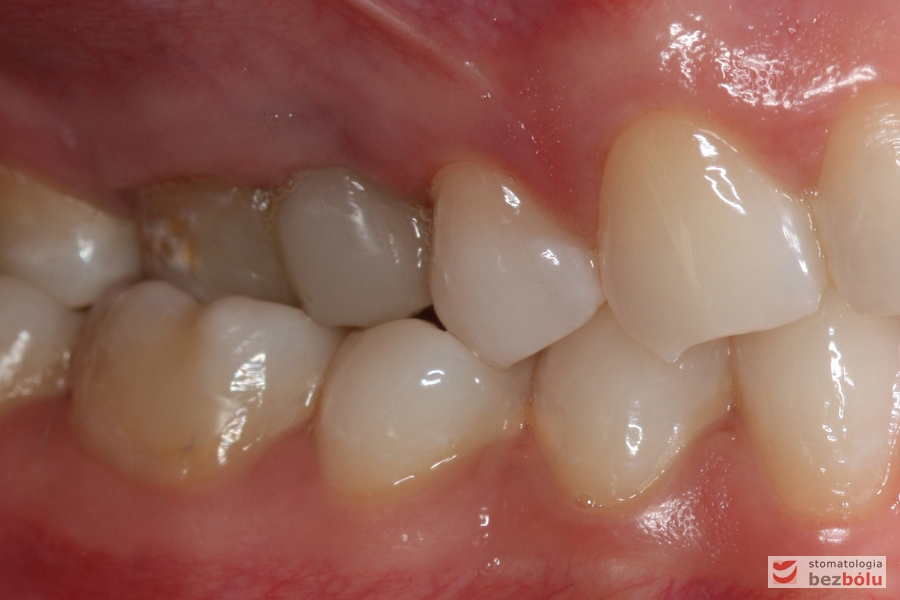

I klasa kłowa i Angle'a - zgryz krzyżowy częściowo boczny, zęby sektora bocznego żuchwy przechylone dojęzykowo

I klasa kłowa i Angle’a – zgryz krzyżowy częściowo boczny, zęby sektora bocznego żuchwy przechylone dojęzykowo

Prawa strona w zgryzie - korona prowizoryczna na pierwszym trzonowcu

Prawa strona w zgryzie – korona prowizoryczna na pierwszym trzonowcu